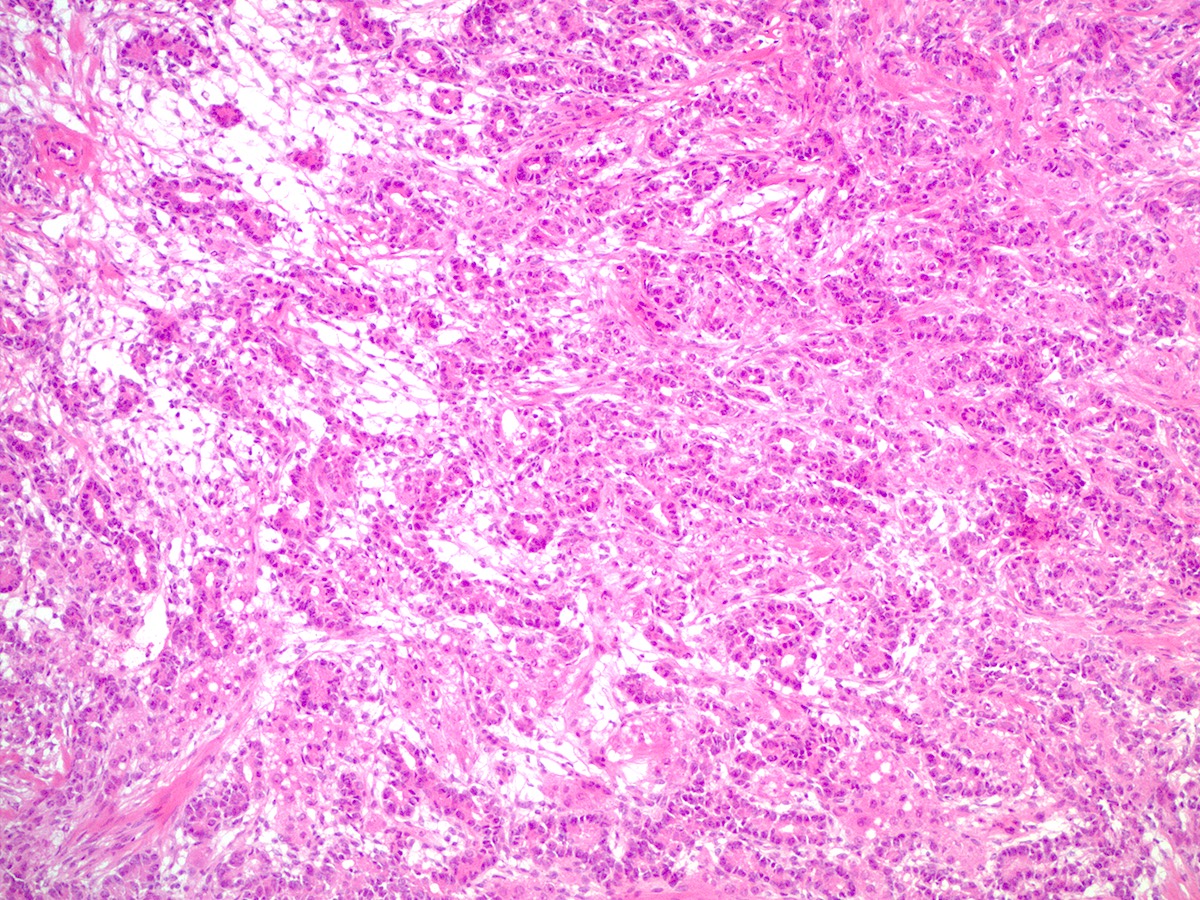

Microscopic (histologic) description

- Difficulty of histologic diagnosis increases with tumor grade

- Moderately differentiated

- Typically has a diffuse or lobulated architectural pattern and may show alternating hypo and hypercellularity on low magnification

- Sertoli cells form compressed tubules, cords or diffuse sheets and have hyperchromatic, oval or spindled nuclei with mild to moderate atypia and occasional mitotic figures (average 5 per 10 high power fields)

- Rare small clusters of Leydig cells are admixed with the Sertoli cell component

- Follicular differentiation may be seen in moderately and poorly differentiated tumors and may resemble juvenile granulosa cell tumor (Am J Surg Pathol 2021;45:59)